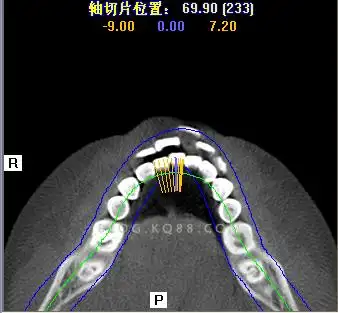

口腔解剖生理学尖牙的髓腔形态

前牙及双尖牙解剖ppt课件